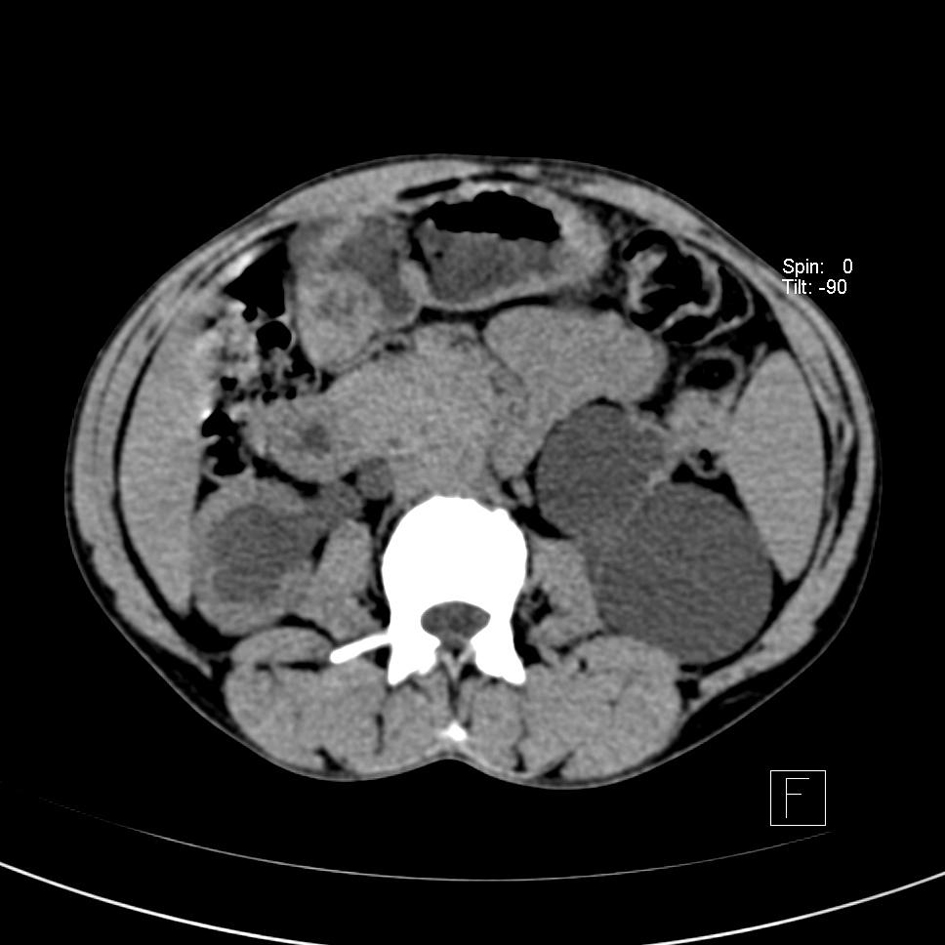

Ultrasonograph of abdomen revealed bilateral hydroureteronephrosis with hardly any parenchyma on left side with ectopic opening of ureters in the proximal prostatic urethra. TRUS examination showed non-visualized left seminal vesicle in addition to the above findings. Non-contrast CT (Fig. 1-3) and MRI showed the anatomical details but no ureterocele was reported. No vesicoureteric reflux was seen in the voiding cystourethrogram film.

![]() Click for large image | Figure 1. CT abdomen showing bilateral hydronephrosis with hardly any parenchyma on the left side. |